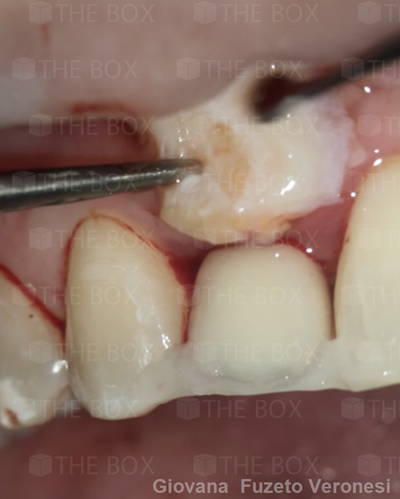

Infra bony defect one wall defect follow up 18 months show regeneration of buccal bone and interdental defect utilizing allograft bone substitute